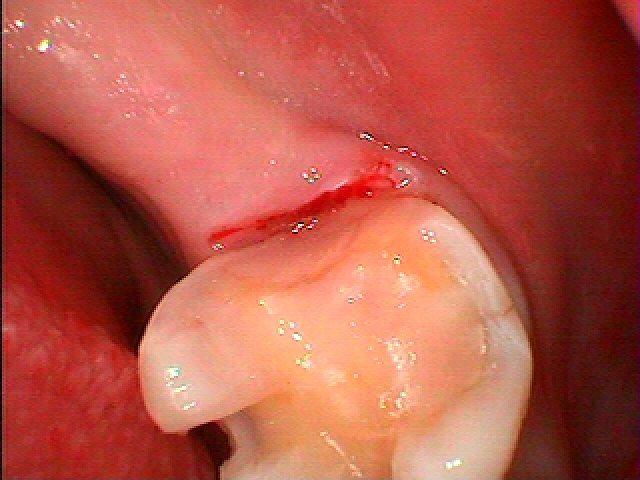

銀歯の下は基本このように悪くなっていることが多いです。| |広島市安佐南区の歯科医院 銀歯の下は基本このように悪くなっていることが多いです。 トップ お知らせ・ブログ 銀歯の下は基本このように悪くなっていることが多いです。 銀歯の下は基本このように悪くなっていることが多いです。 Web診療予約 初めての方へ 選ばれ続ける理由 院内設備について 歯が痛いしみる一般歯科 歯がぐらぐらする歯周病 健康な歯を保ちたい予防歯科 子供の虫歯予防をしたい小児歯科 銀歯をセラミックに審美歯科 白い歯を目指しませんか?ホワイトニング 矯正専門医がいるので安心矯正歯科 抜けた歯を補いたいインプラント・入れ歯 医院案内 スタッフ紹介 メリィハウス歯科クリニックオフィシャルホームページ ラベンダー歯科クリニックオフィシャルホームページ お知らせ・ブログ ホーム 診療科目 一般歯科 歯周病治療 予防治療 小児歯科 審美治療 ホワイトニング 矯正歯科 入れ歯・インプラント マウスピース矯正 初めての方へ 院長・スタッフ 設備紹介 医院案内・アクセス メニューを閉じる